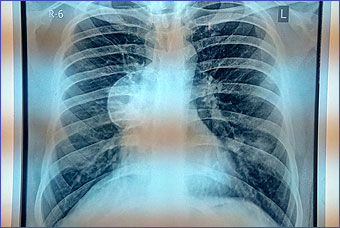

Case 1

A 30 years old male presenting with low grade fever and cough with scanty mucoid expectoration and streaky hemoptysis for last one year. His complaints was subsided with oral co amoxiclav and cough suppressant. He has no chest pain or shortness of breath. Past history revealed tubercular pleural effusion at 4 years of age with ATD completed then. He remained asymptomatic for last 26 years. His chest x-ray and CT scan chest given. Mantoux test is positive showing 10mm induration. His echinococcus IgG is positive in high titre.